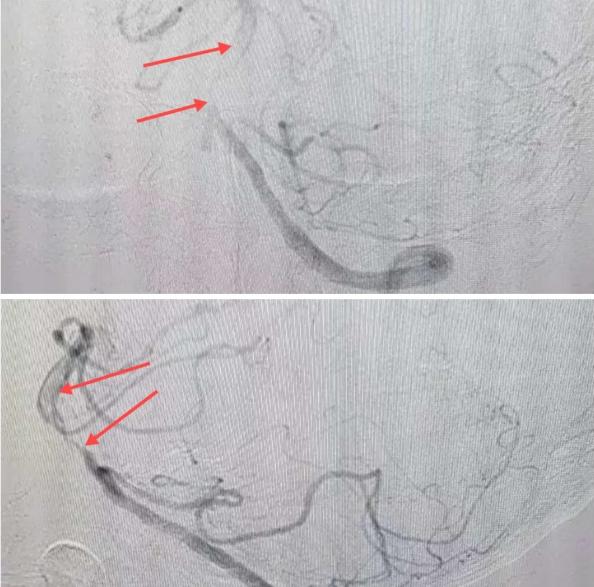

在經(jīng)造影后,主刀醫(yī)生腦一科副主任楊慶堂發(fā)現(xiàn)患者基底動脈下段重度狹窄且狹窄段以遠(yuǎn)有大負(fù)荷血栓,其狹窄處考慮為動脈夾層,手術(shù)難度及風(fēng)險(xiǎn)較大。楊慶堂副主任在彭壯副主任醫(yī)師的協(xié)助下運(yùn)用spaceman(太空人)技術(shù),中間導(dǎo)管抵近血栓抽吸配合支架拉栓,成功開通血管。再次造影可見基底動脈管腔明顯增寬,遠(yuǎn)端血管顯影良好,且等待20分鐘后造影仍顯示血流通暢。楊慶堂副主任考慮到本次手術(shù)時(shí)間不宜過長,現(xiàn)患者基底動脈及分支前向血流維持良好,給予其抗栓藥物應(yīng)用后結(jié)束手術(shù),并建議患者3個月后復(fù)查造影,明確其基底動脈夾層情況。

造影可見血管夾層和大量血栓形成

取栓后血管管腔增寬,前向血流良好